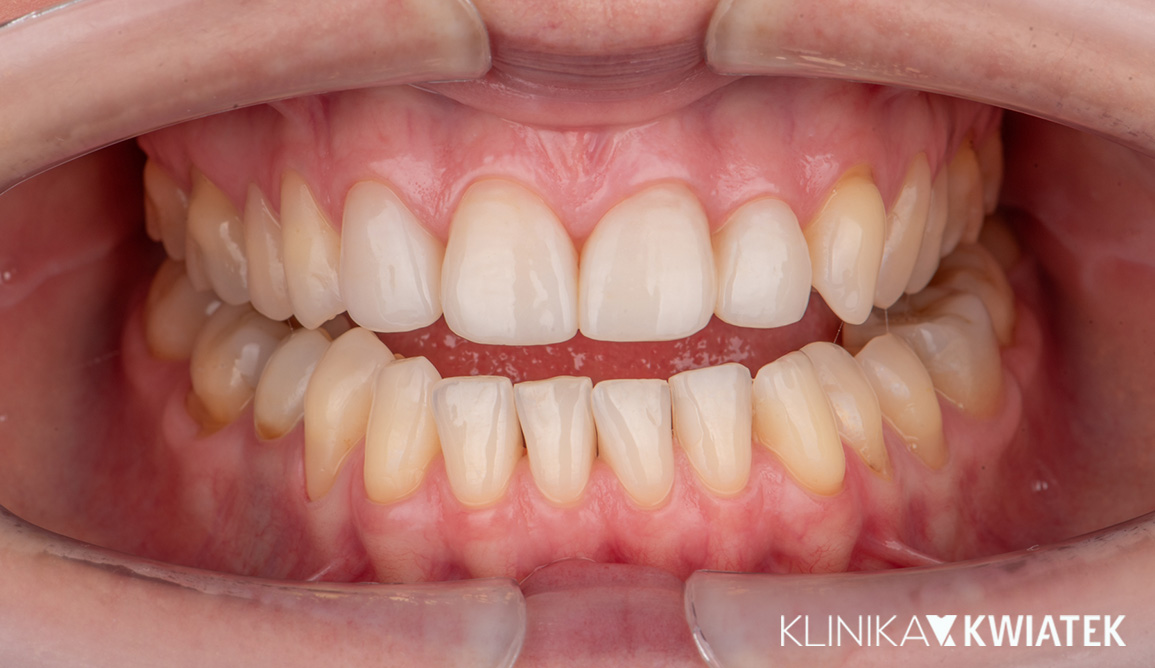

PRZED

PO

Pacjentka zgłosiła się z licznymi ubytkami, znacznym starciem zębów oraz objawami przeciążenia zgryzu wynikającymi z wieloletniego zaciskania i zgrzytania. Po pełnej diagnostyce przeprowadzono higienizację, leczenie zachowawcze, endodontyczne i szynoterapię, a następnie ortodoncję oraz finalną odbudowę estetyczno-protetyczną wszystkich startych powierzchni zębów. Efektem jest stabilny, zdrowy zgryz, prawidłowa praca stawów oraz harmonijny, trwały i estetyczny uśmiech Pacjentki.